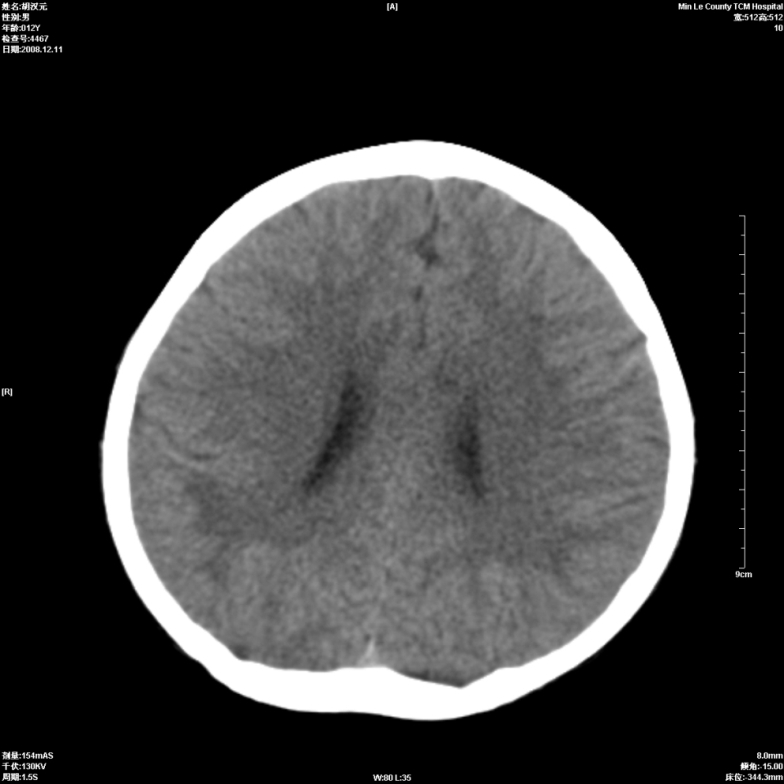

标题: PED1681:头疼发热约一周 [打印本页]

标题: PED1681:头疼发热约一周

颅脑未见确切异常。必要时进一步检查,如mri、脑脊液检查。

两侧顶部近灰质处白质密度降低,是否炎性改变

颅脑ct轴位平扫颅内未见明确异常;建议必要时复查或行进一步检查。

两侧顶部近灰质处白质密度降低,建议mri